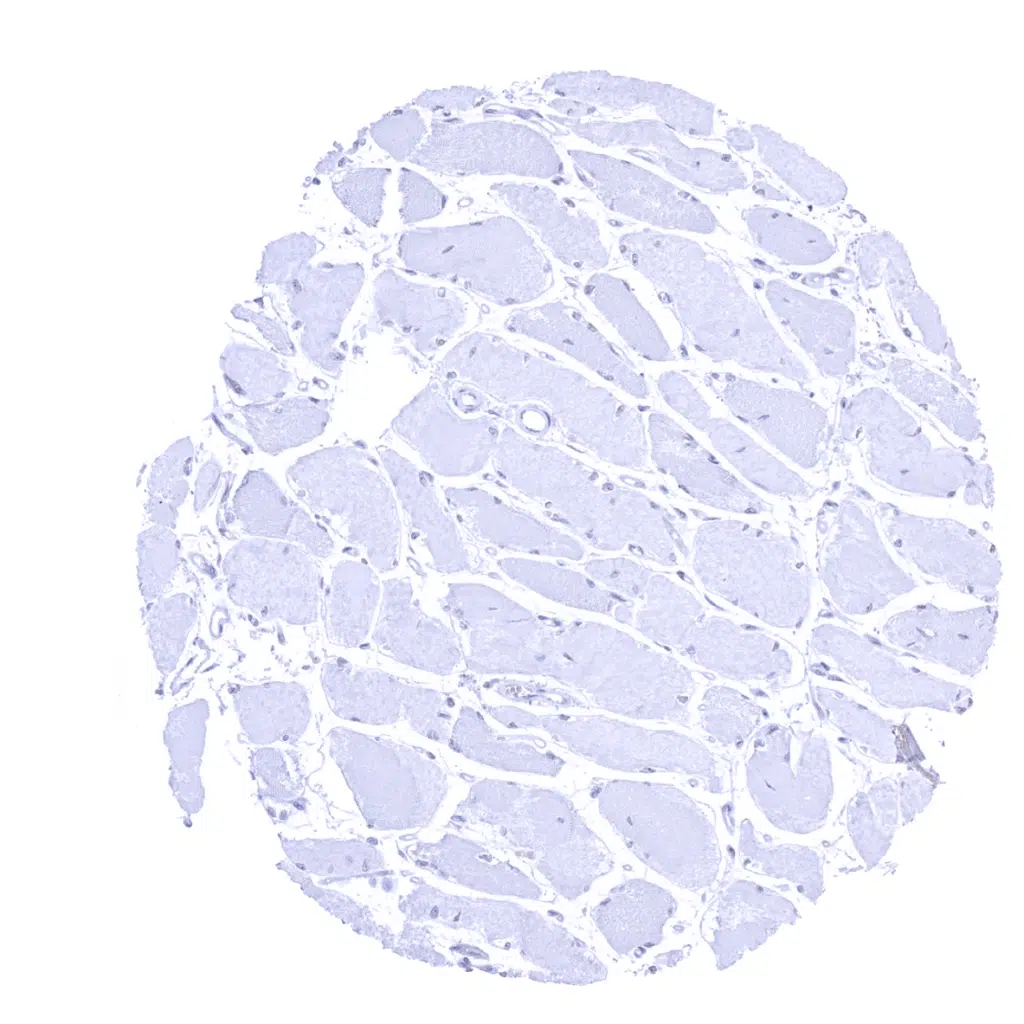

Skeletal muscle